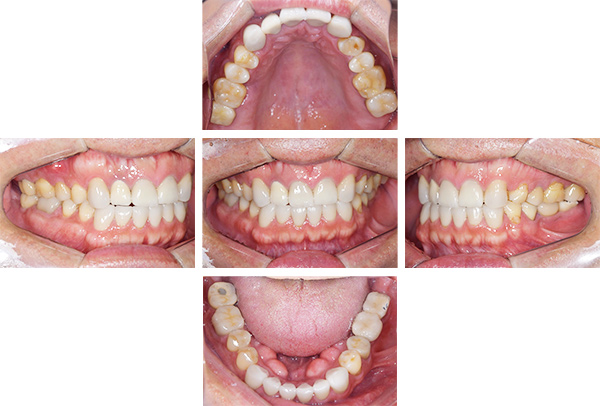

インレー症例

治療前

治療後

治療期間 4回(1ヶ月)

費用 ・セラミックインレー10本

合計:550,000円

治療リスク・副作用 ・詰め物、被せ物をする時は自分の歯を削ることになります

・歯ぎしり・食いしばりが強い方は、セラミックが割れてしまうことがあります。